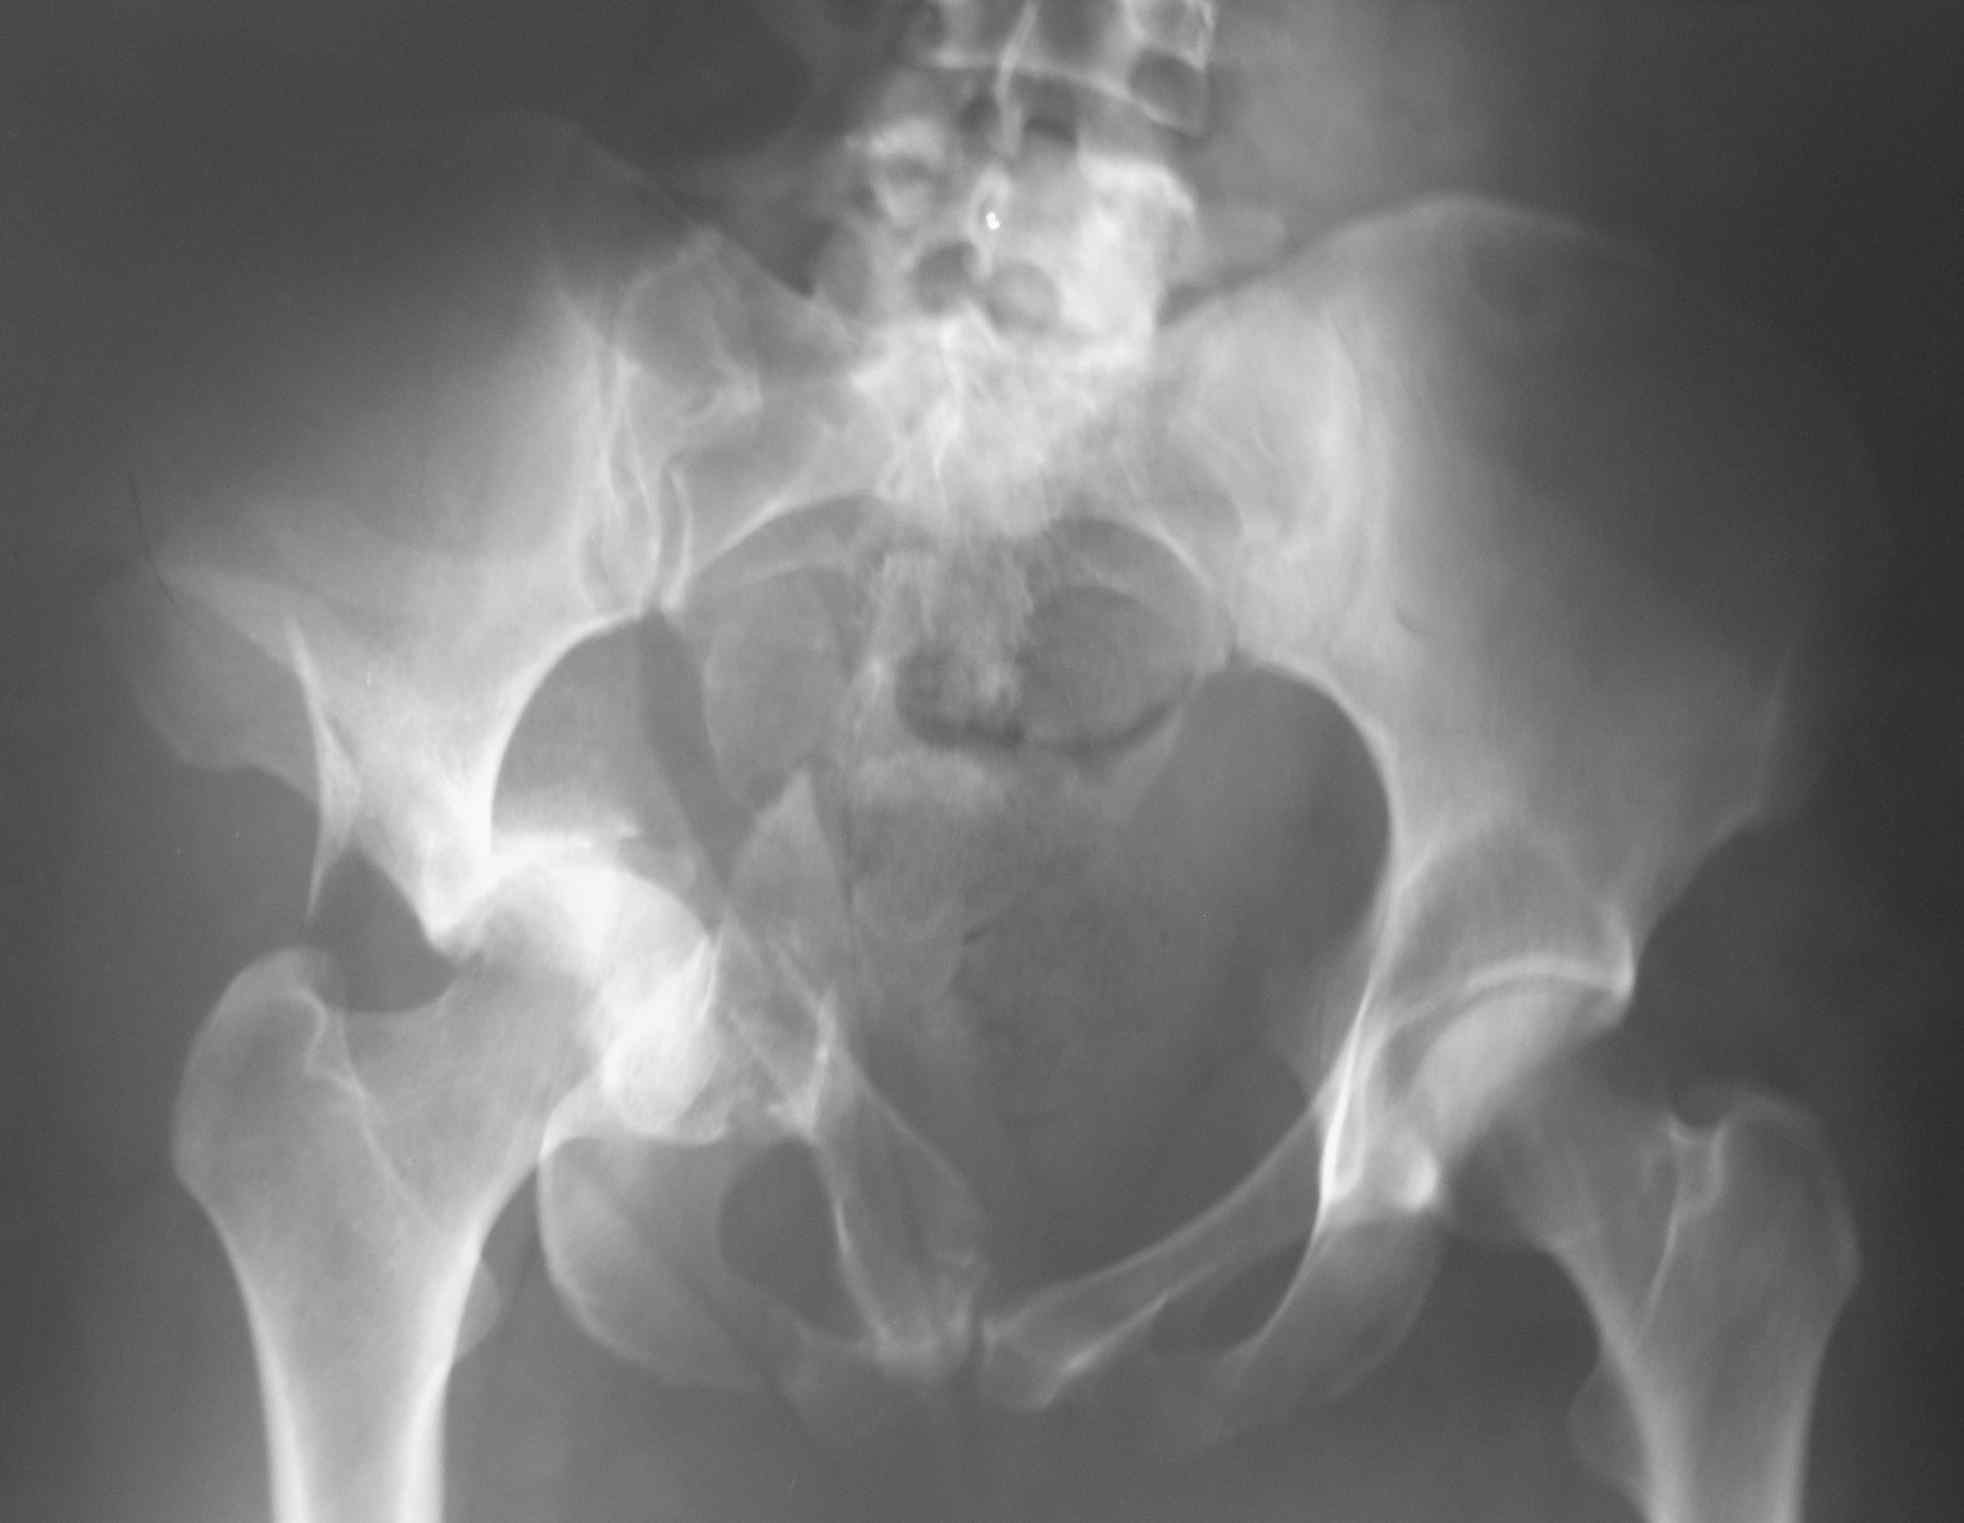

Это не "цетральный вывих", а двухколонный перелом вертлужной впадины. Лучше прооперировать, я бы выбрал подвздошно бедренный доступ, хотя можно и из бокового чрезвертельного.

Оскольчатый двухколонный перелом, лучше отправить пациента туда, где занимаются лечением "центральных вывихов" бедра.

Тут перелом достаточно сложный и говорить о характере перелома можно после дополнительных методов исследования. Нужны проекции Judet для оценки передней и задней колонн (перелома передней и задней колонн видны и на этом снимке, но характер их перелома и смещение лучше видны в специальных порекциях). Нужно КТ исследование.

Большое спасибо за содержательные советы. Вот снимок при поступлении.

Это круто - пытаться отрепонировать двухколонный оскольчатый перелом в.впадины в палате - кроме усиления кровотечения манипуляция ни к чему не приведет - это же абсолютно нестабильная ситуация. Эндопротезирование не панацея для нелеченного перелома впадины - через 7-10 дней с момента травмы при стабилизации состояния больной должен быть выполнен остеосинтез. Если опыта хирургии впадины нет, то лучше переведите больную в больницу, где этим методом владеют. Перелом сложный, кроме фиксации колонн рекон.пластинами потребуются и фолк пластины для фиксации квадрилатерной пластины.

На основании одной проекции трудно определить к какому перелому вертлужной впадины относится данный перелом, тем более подсказать "подвздошно бедренный доступ, хотя можно и из бокового чрезвертельного" оперативный доступ. Нужны обязательные стандартные рентген снимки по Judet: прямой и косые снимки, из косых запирательный и подвздошные снимки ацетабулума. Рентген снимки и Компьютерную Томограмму лучше сделать после скелетнего вытяжения.